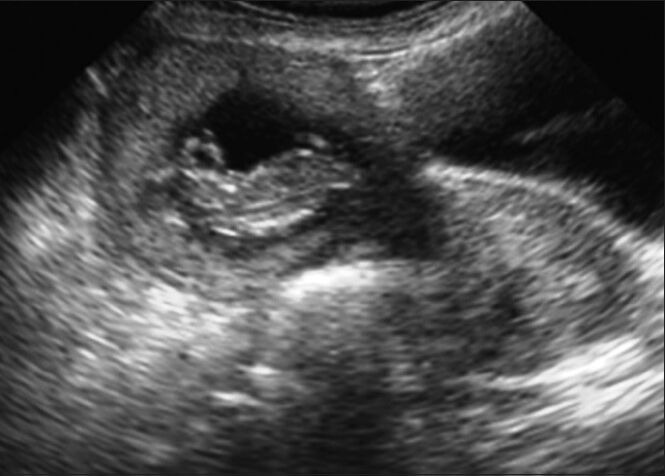

A non-communicating rudimentary horn is an uncommon site for ectopic pregnancy. Rudimentary horn pregnancy (RHP) is a rare entity but associated with grave clinical consequences. Majority of these cases if not detected timely end up in uterine rupture and present as an obstetrical emergency. We present this case of a 32-year-old, third gravida with a 12 weeks live gestation in the right rudimentary horn, which was successfully managed with laparoscopic resection. Early diagnosis is the key stone in the management of such cases. Laparoscopic resection is a safe and viable option in the surgical management of unruptured RHP.